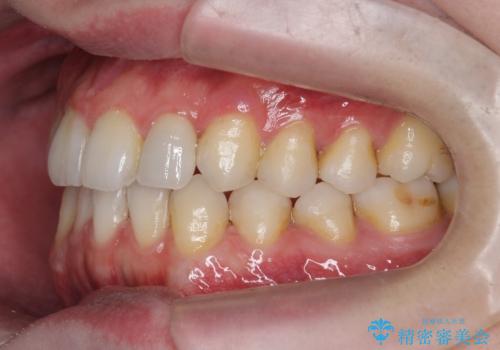

前歯の矮小歯 奥歯の反対咬合 をインビザラインで

- 上下の前歯が気になり来院。

左上2が矮小歯で小さく、また、左の奥歯が反対咬合になっていました。

左上2番はセラミッククラウンで反対側と同じ大きさにしました。

インビザラインでの臼歯の反対咬合の治療は難しいことが多いです。

今回は下の前歯を1本抜くことで、下の奥歯をしっかり内側に傾けて治療を行いました。